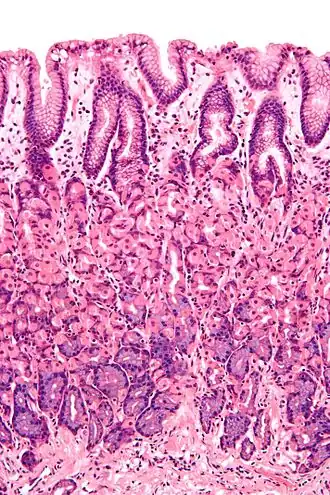

Histological section taken from the gastric antrum, showing the mucosa of the stomach

The mucosa is composed of one or more layers of epithelial cells that secrete mucus, and an underlying lamina propria of areolar connective tissue.[1] The type of cells and type of mucus secreted vary from organ to organ and each can differ along a given tract.[2][3]